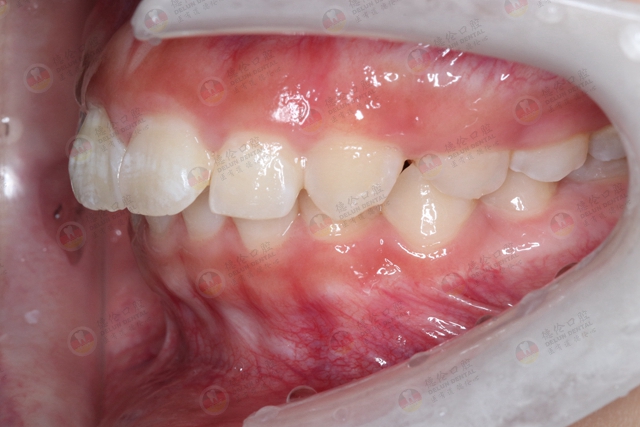

只有牙齿不齐的人需要矫正吗?

牙齿矫正并非是指把牙齿排整齐那么简单,还包括改善牙齿的咬合关系和功能,改善面部形态,软组织侧貌的美观等目的。所以除了牙齿不齐之外,咬合不对可能造成颞下颌关节紊乱,甚至有可能造成偏头痛,咀嚼效率低下,影响身体健康等。生活中常见的龅牙、地包天、牙齿之间缝隙过大等都需要进行矫正。